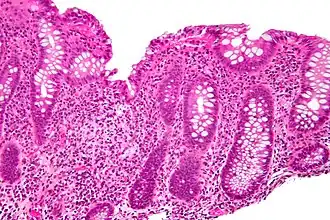

In histology, cryptitis refers to inflammation of an intestinal crypt.

Cryptitis is a non-specific histopathologic finding that is seen in several conditions, e.g. inflammatory bowel disease,[1] diverticular disease,[2] radiation colitis,[3] infectious colitis.

Cryptitis. H&E stain. -